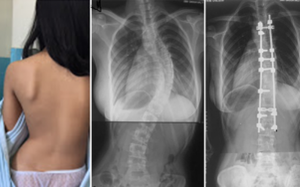

Từ 10/6, tại BV Bạch Mai, trẻ em bị cong vẹo cột sống và người lớn có bệnh lý về cột sống sẽ có cơ hội được khám sàng lọc và tư vấn miễn phí bởi các bác sỹ Khoa Chấn thương...